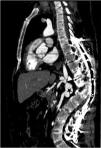

A 43-year-old male patient with a history of neurofibromatosis type 1 (NF-1) was referred to our hospital for resistant arterial hypertension. At physical examination he presented asymmetric elevated blood pressure in the extremities, higher in the upper limbs. An echocardiogram was performed and showed moderate left ventricular hypertrophy, without signs of coarctation of the aorta. As a part of workup for hypertension, computed tomography (CT) was performed, which showed an abnormal aorta with severe narrowing and a saccular aneurysm at the level of the renal arteries (Figures 1 and 2). There was extensive collateral blood flow through hypertrophic lumbar, epigastric and mesenteric arteries and the left renal artery showed subtotal stenosis at its origin, causing atrophy of the left kidney (Figure 3). Additional angiographic study enabled a final diagnosis. There were also subcutaneous and retroperitoneal neurofibromas.